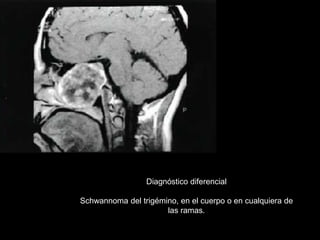

Diagnóstico diferencial

Schwannoma del trigémino, en el cuerpo o en cualquiera de